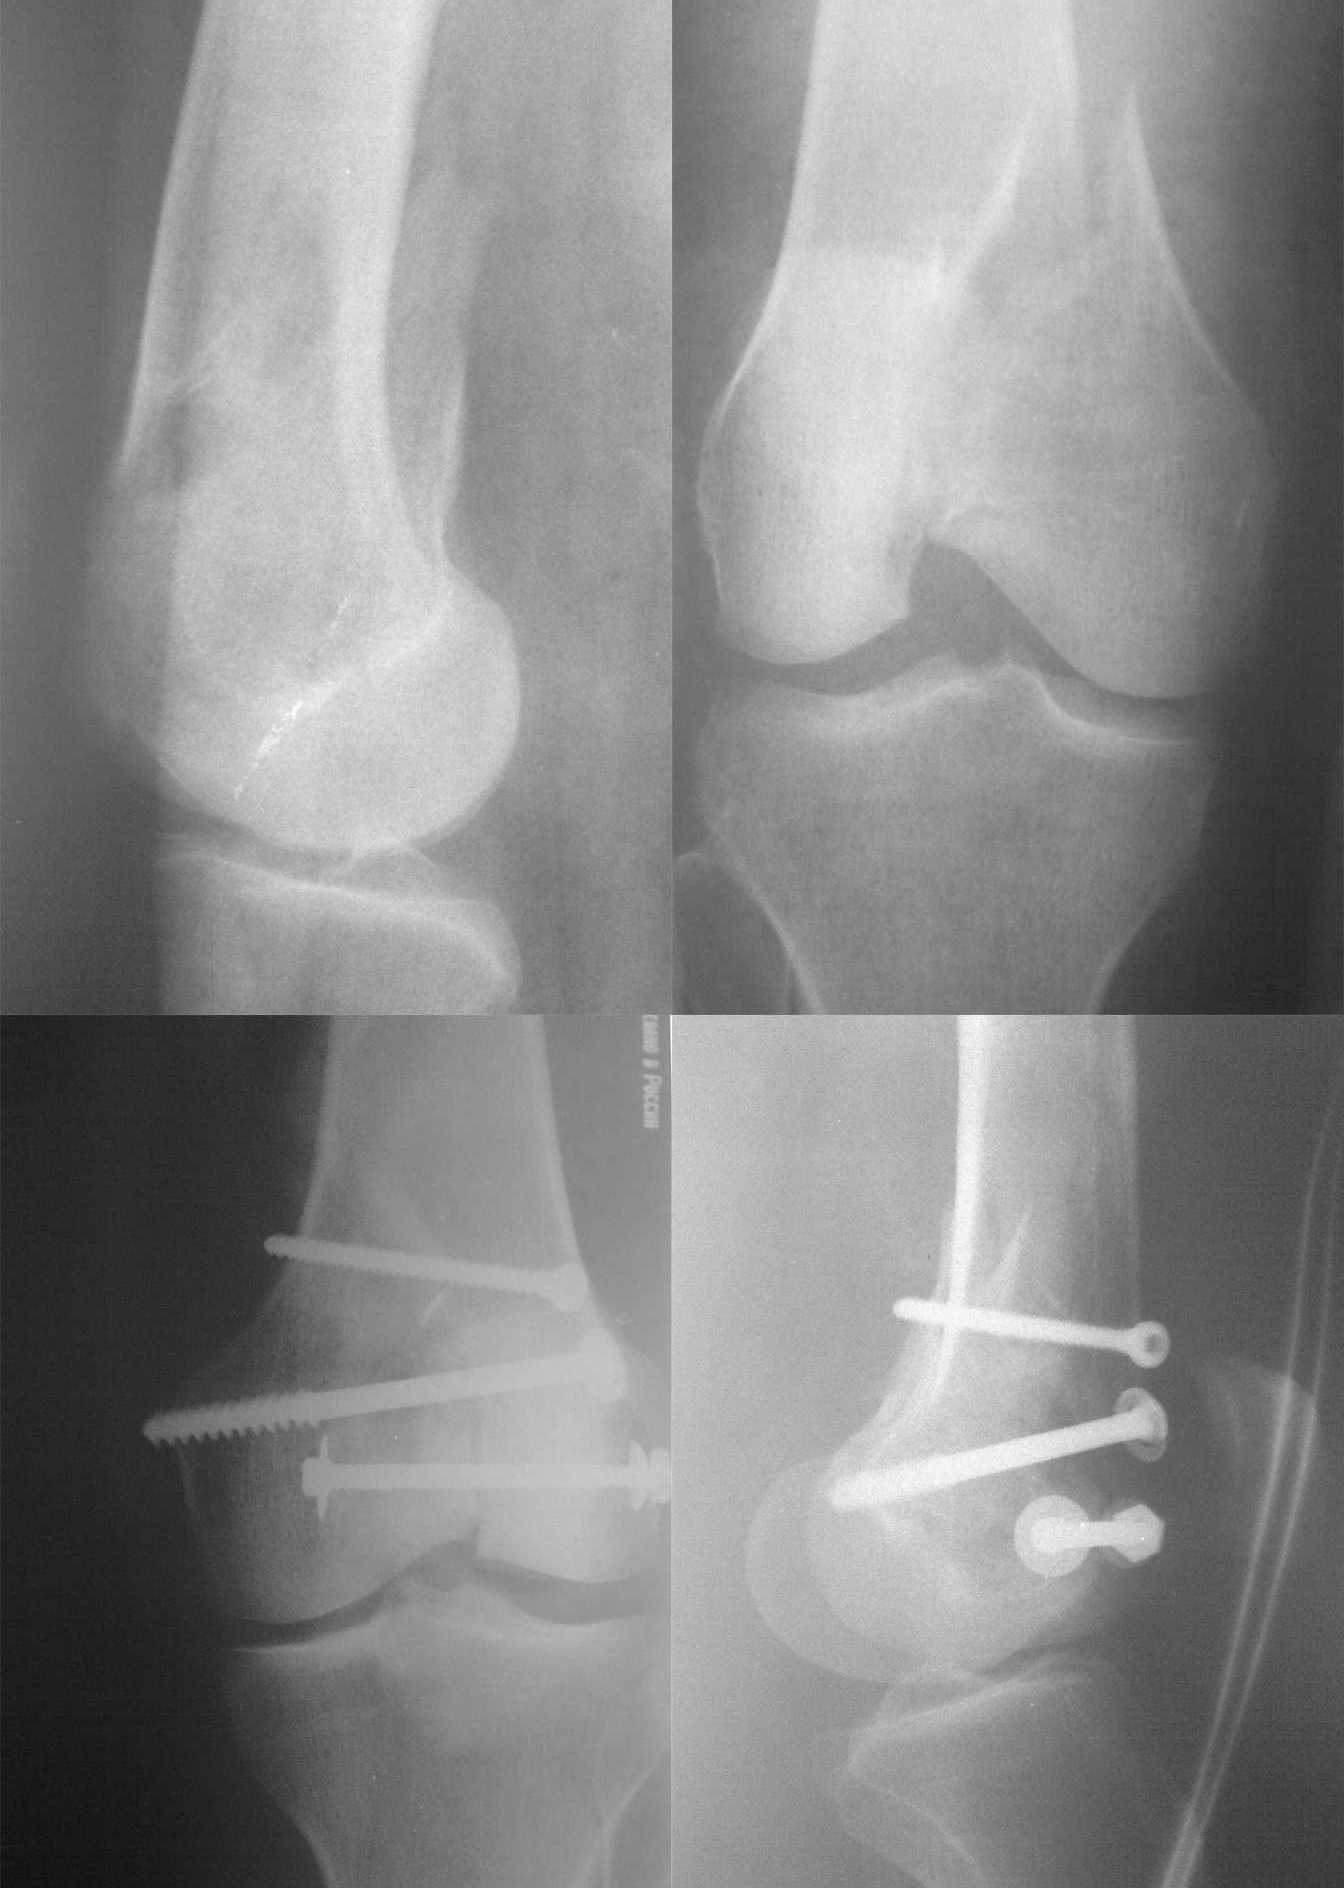

синтез мыщелка бедра

Уважаемые коллеги выскажите пожалуйста ваше мнение

по поводу остеосинтеза свежего перелома внутреннего мыщелка бедра